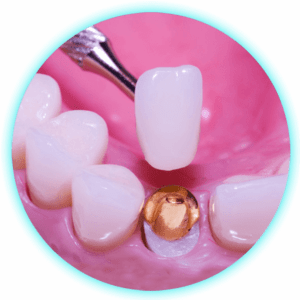

Cementacion de Coronas – Puentes

$25,00 -